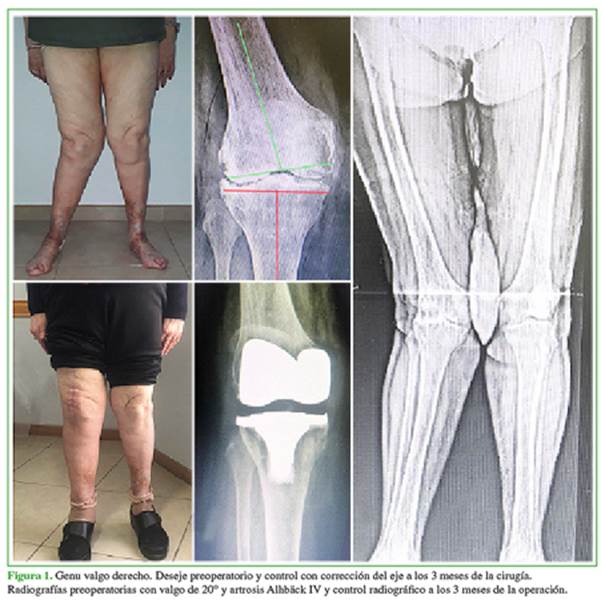

Las mediciones radiográficas de corrección del deseje fueron: ángulo femorotibial preoperatorio promedio: valgo 27º (rango 21-39) y ángulo femorotibial posoperatorio promedio: valgo 6,2º (rango 4-10) (Figuras 1 y 2).